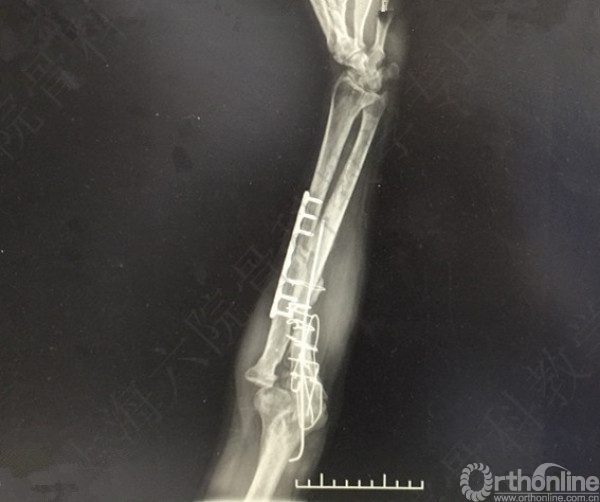

患者左尺桡骨多发骨折伴肘关节脱位,术后2年,桡神经损伤,左拇指伸受限。

X线及CT示:左尺桡骨骨不连,尺骨力线差,成角,桡骨头脱位,创伤性关节炎。

患者择期行左尺桡骨取原内固定+切开复位内固定术+髂骨异体骨植骨+桡骨头切除术。

术后X线片示:左尺桡骨骨不连术后,对位对线可,内固定牢靠,桡骨头切除,肘关节在位。

医方第一次术后,未能纠正骨折力线,未发现桡骨头脱位,手术方式和操作欠妥当。存在对疾病评估不足,漏诊,手术方式不当,手术操作不当,术后并发症观察及处理不当等过失。